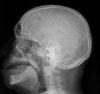

What is on your list of differential diagnoses for a 55 year old patient with an aggressive radiographic lesion, and raindrop skull?

A

1. Multiple myeloma

2. mets

3. lymphoma

What is the term for the radiographic sign that is characteristic of multiple myeloma in the skull?

raindrop skull